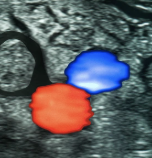

The Premium Screening is Executive Health’s most extensive medical examination - offering a full overview of your health in just one visit.Through high-resolution MRI imaging, advanced laboratory analysis and specialist consultation, we detect potential risks before symptoms appear. Our experienced physicians provide clear answers and personal guidance, helping you stay healthy, informed and in control.

By identifying risks early, we improve the chances of long-term wellbeing.